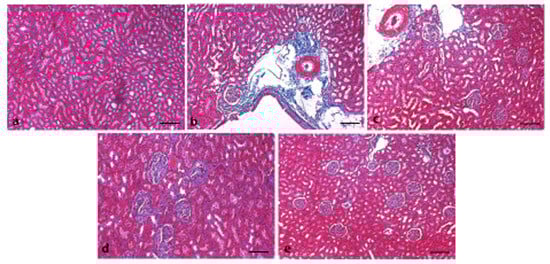

3.6. Effect of 6-Gingerol on Kidney Architecture

3.7. Effects of 6-Gingerol on TNF-α Expression